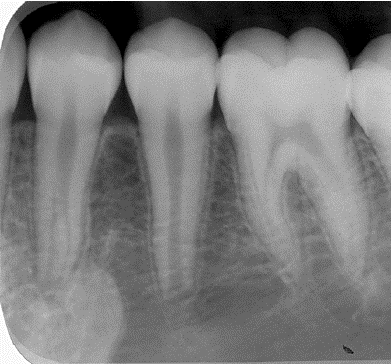

2. (Select ONE OR MORE correct answers)

The radiograph shows evidence of